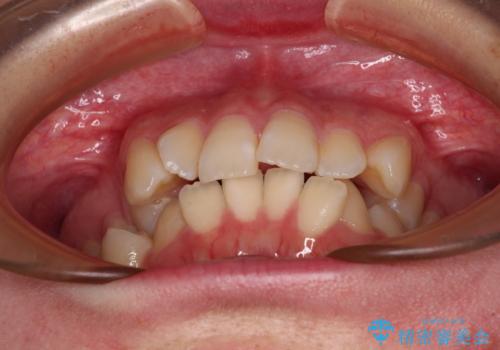

- 上下前歯のデコボコを気にして来院された患者様です。

口元の突出感はあまりなかったものの、デコボコを非抜歯で改善すると出っ歯になる可能性があるため、上下左右の第一小臼歯4本を抜歯し、ワイヤー装置にて矯正治療を行うこととしました。

口元の突出感はなかったものの、捻転や八重歯を改善するために補助装置を併用する必要がありました。